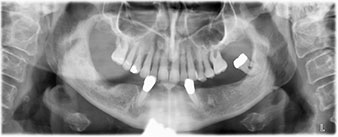

È stata eseguita una tomografia computerizzata Dentale Cone Beam in 3D (CBCT, con Planmeca) per aiutare la programmazione dell'intervento e la riduzione di rischi. L'esame ha evidenziato che la qualità e quantità dell'osso disponibile era sufficiente per eseguire l'intervento e la ricostruzione immediata, utilizzando il metodo Fast & Fixed. In base al protocollo del sistema, gli impianti sono stati inseriti in posizione 35, 32, 42 e 45. Gli impianti distali vengono installati a un angolo massimo di 45 gradi. Così facendo, il profilo che ne risulta viene spostato in posizione posteriore, generando un poligono di supporto più ampio (Fig. 3).